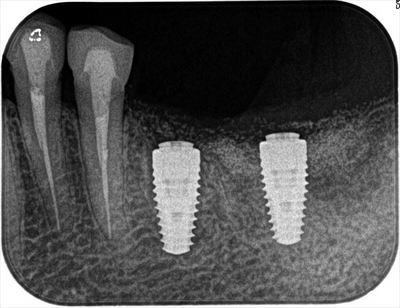

オペ終了時のレントゲン写真です。

埋入トルクは充分でしたので6週後には仮歯で咬んでいただける予定です。